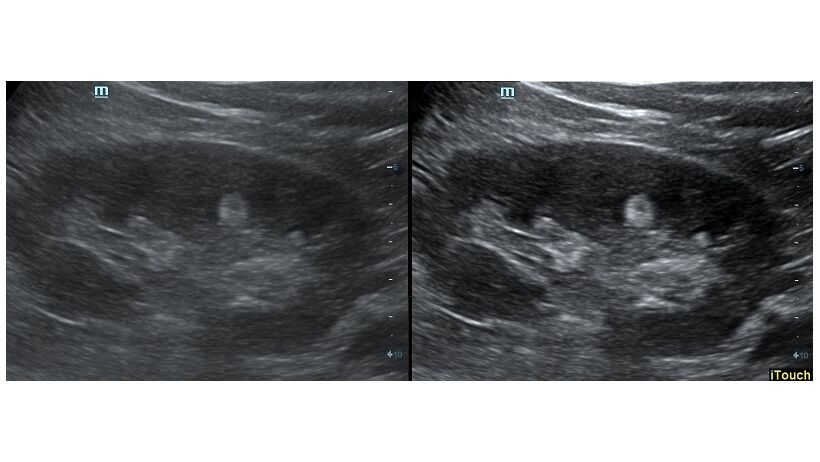

Оптимизация изображения происходит и за счет постобработки. Наиболее часто используемый инструмент - общее усиление (Gain). Усиление делает изображение «ярче», но чем сильнее усиление, тем меньше различия между структурами. Также используются усиление по времени (TGC) и усиление по длине (LGC), которые позволяют изменять отображение на экране послойно, позволяя подсветить гипоэхогенные участки, или, наоборот, снизить визуально эхогенность слишком ярких моментов. Данный вид оптимизации требует много времени, для упрощения работы доктора на приборах Mindray внедрена система автоматической оптимизации - iTouch.